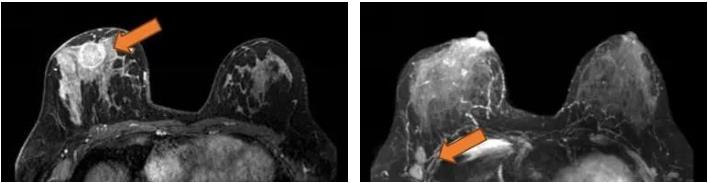

2021.7.6 钼靶示:右乳外上象限肿块,考虑乳腺癌(BI-RADS-5类)右腋下肿大淋巴结,M灶可能。

右乳外上象限不规则高密度肿块,边缘毛糙,大小约3.3×2.7cm,邻近皮肤牵拉增厚,右腋下见肿大淋巴结。

图2. 钼靶

(3 cycle 后)2021.9.21 钼靶示:右乳外上象限不规则形肿块明显缩小,右腋窝淋巴结亦较前缩小。

图6. 钼靶